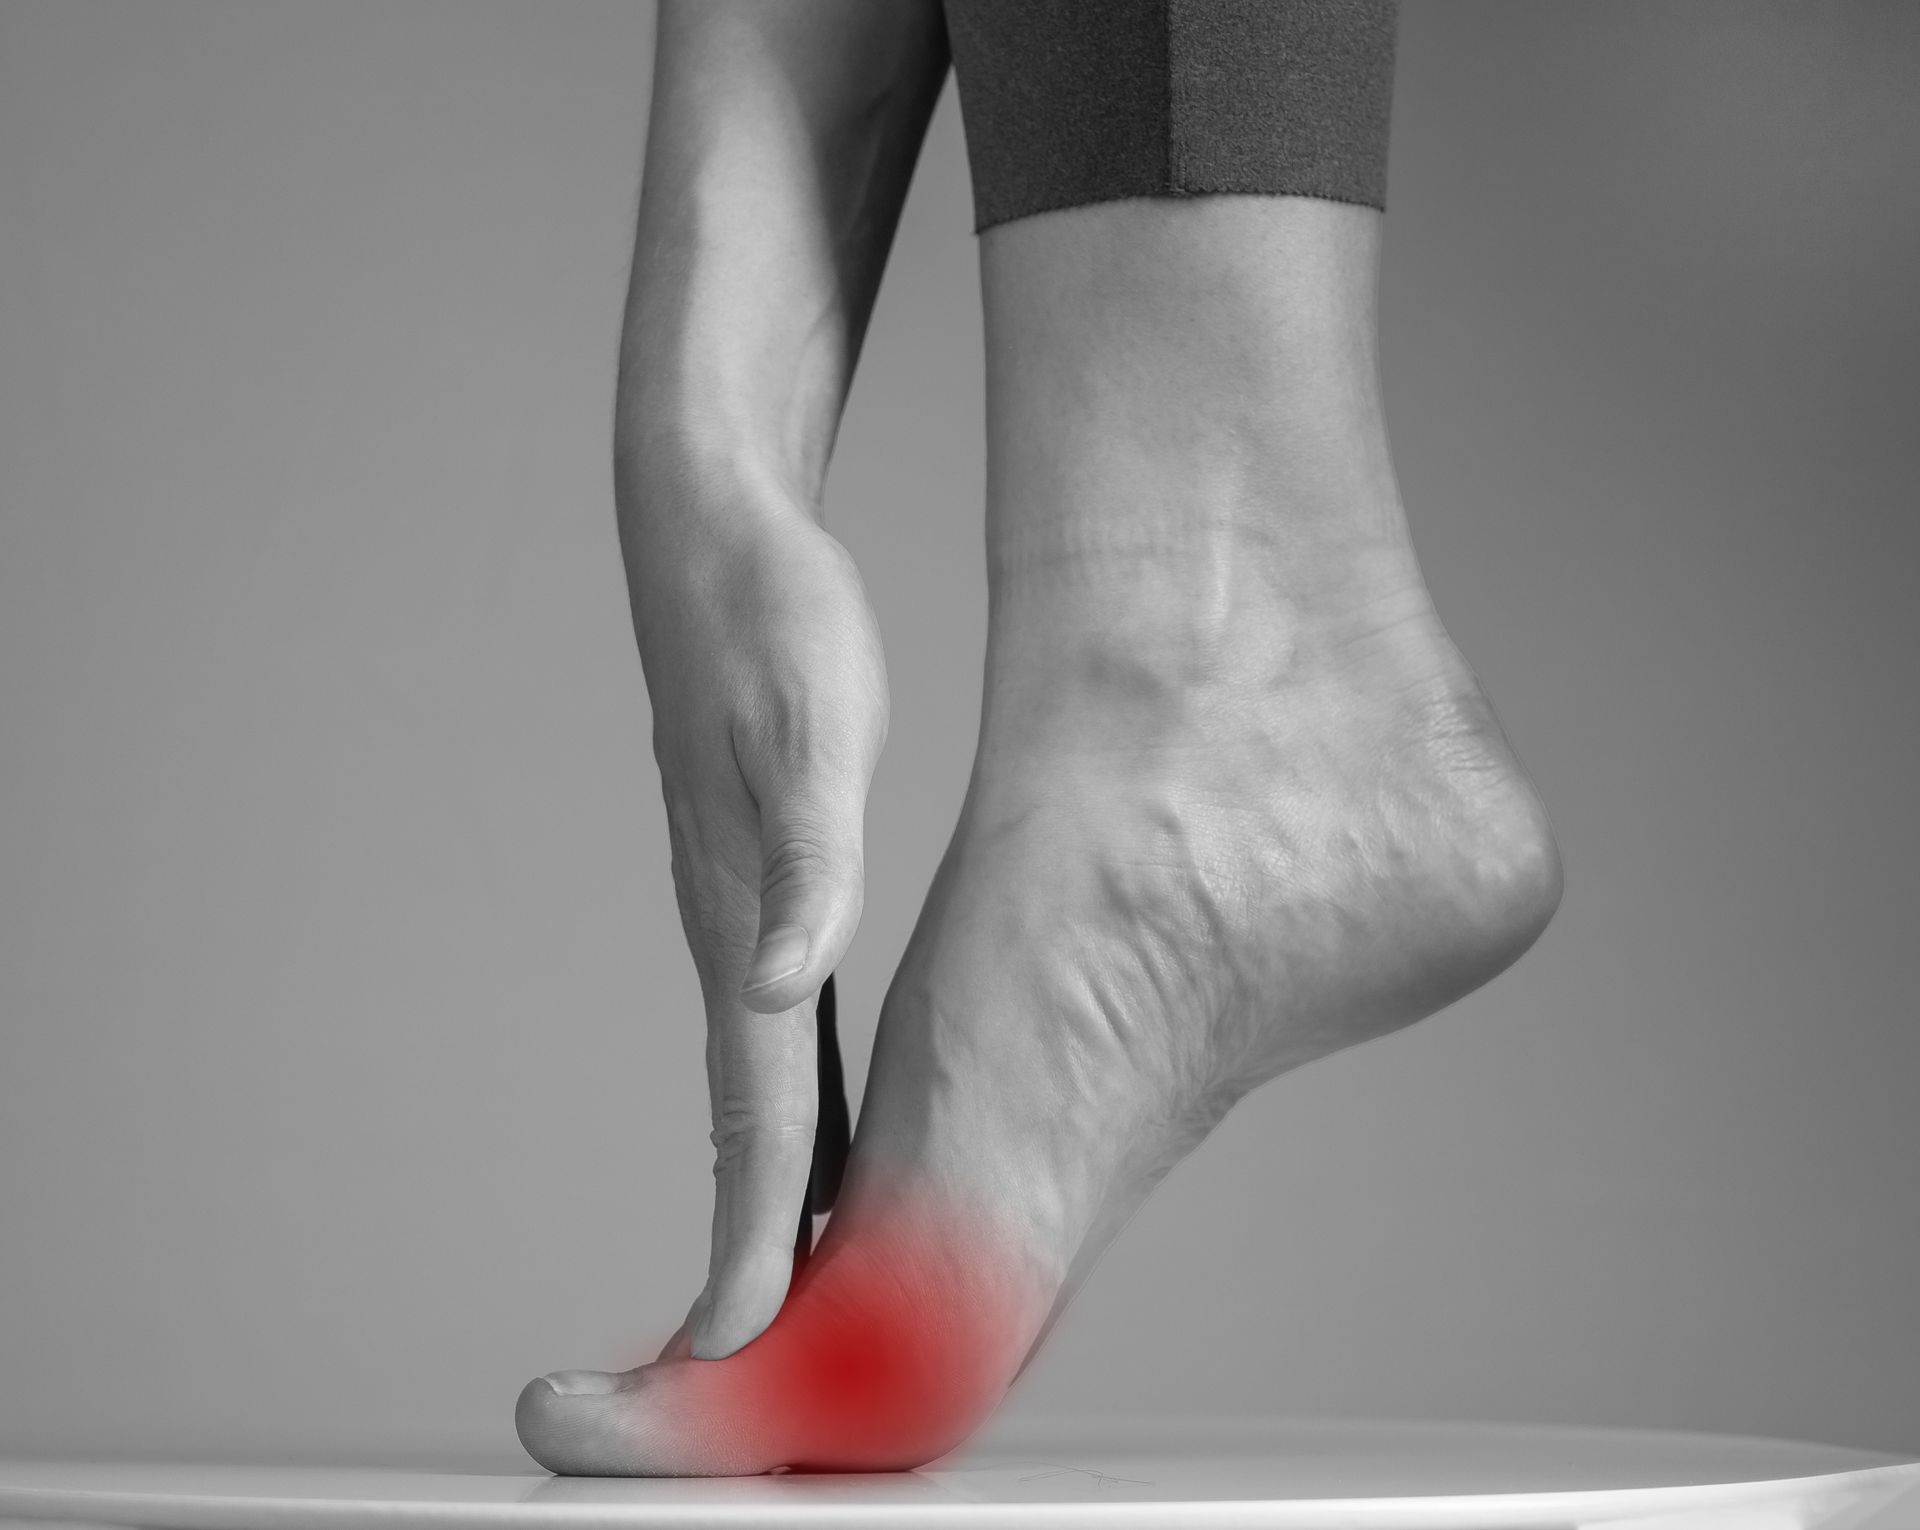

Podiatric medicine focuses on diagnosing and treating conditions of the foot, ankle, and lower leg. Podiatrists provide comprehensive care through exams, accurate diagnoses, and effective treatments. They can perform surgery when needed, prescribe medications, recommend therapeutic exercises, fit custom orthotics, and guide patients on footwear, prevention, and lifestyle choices to support long-term foot and ankle health.